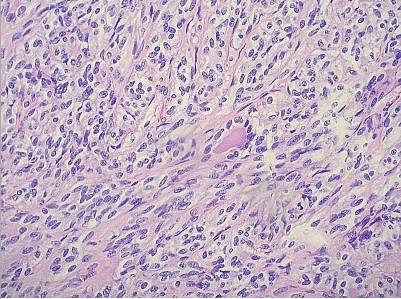

诊治经过:入院后完善血常规、肝肾功、肿瘤标志物均未见明显异常。浅表淋巴结超声检查未见明显异常长大淋巴结。头颅MRI检查及PET-CT未见明显转移征象。于2019年5月13日行电子支气管镜检查,镜下见右肺中间段支气管菜花样新生物完全阻塞管腔,表面覆盖较多炎性坏死物质,组织松散(见图1)。术后病理检查提示为曲菌病。遂给予伏立康唑200mg口服q12h治疗,后于2019年5月15日,2019年5月17日及2019年5月20日行支气管镜下冷冻活检,病理组织检查均提示为炎性坏死组织,于2019年5月23日行CT引导下经皮肺穿刺检查,提示为慢性炎。于2019年5月27日再次行支气管镜下冷冻活检,术后证实为梭形细胞癌,免疫组化为EMA(-),Vim(+),SMA(+),Desmin(-),CD34(-),CD99(+),Ki67(+)30%。后患者于上级医院行手术治疗,术后病理检查提示为鳞状细胞癌并梭形细胞癌。

SCC镜下仅由恶性梭形细胞组成,可粘附呈巢状、漩涡状或不规则束状紧密排列,核分裂相多见,可见肉瘤样生长及局灶性和分散的淋巴浆细胞围绕并浸润肿瘤实质[7]。偶尔可被大量炎性渗出物所覆盖或混合[8],导致其与炎症相混淆,此患者电子支气管镜下可见明显炎性坏死物,经4次电子支气管镜冷冻活检及肺穿刺活检均提示为炎症改变,在第5次支气管镜下冷冻活检时才确诊,可能与此因素有关。